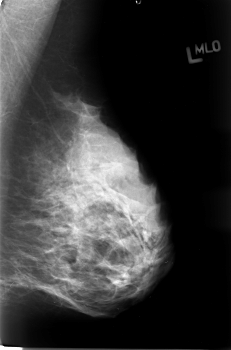

B_3033_1.LEFT_CC

LEFT_CC LINES 4616 PIXELS_PER_LINE 3104 BITS_PER_PIXEL 12 RESOLUTION 50 OVERLAY